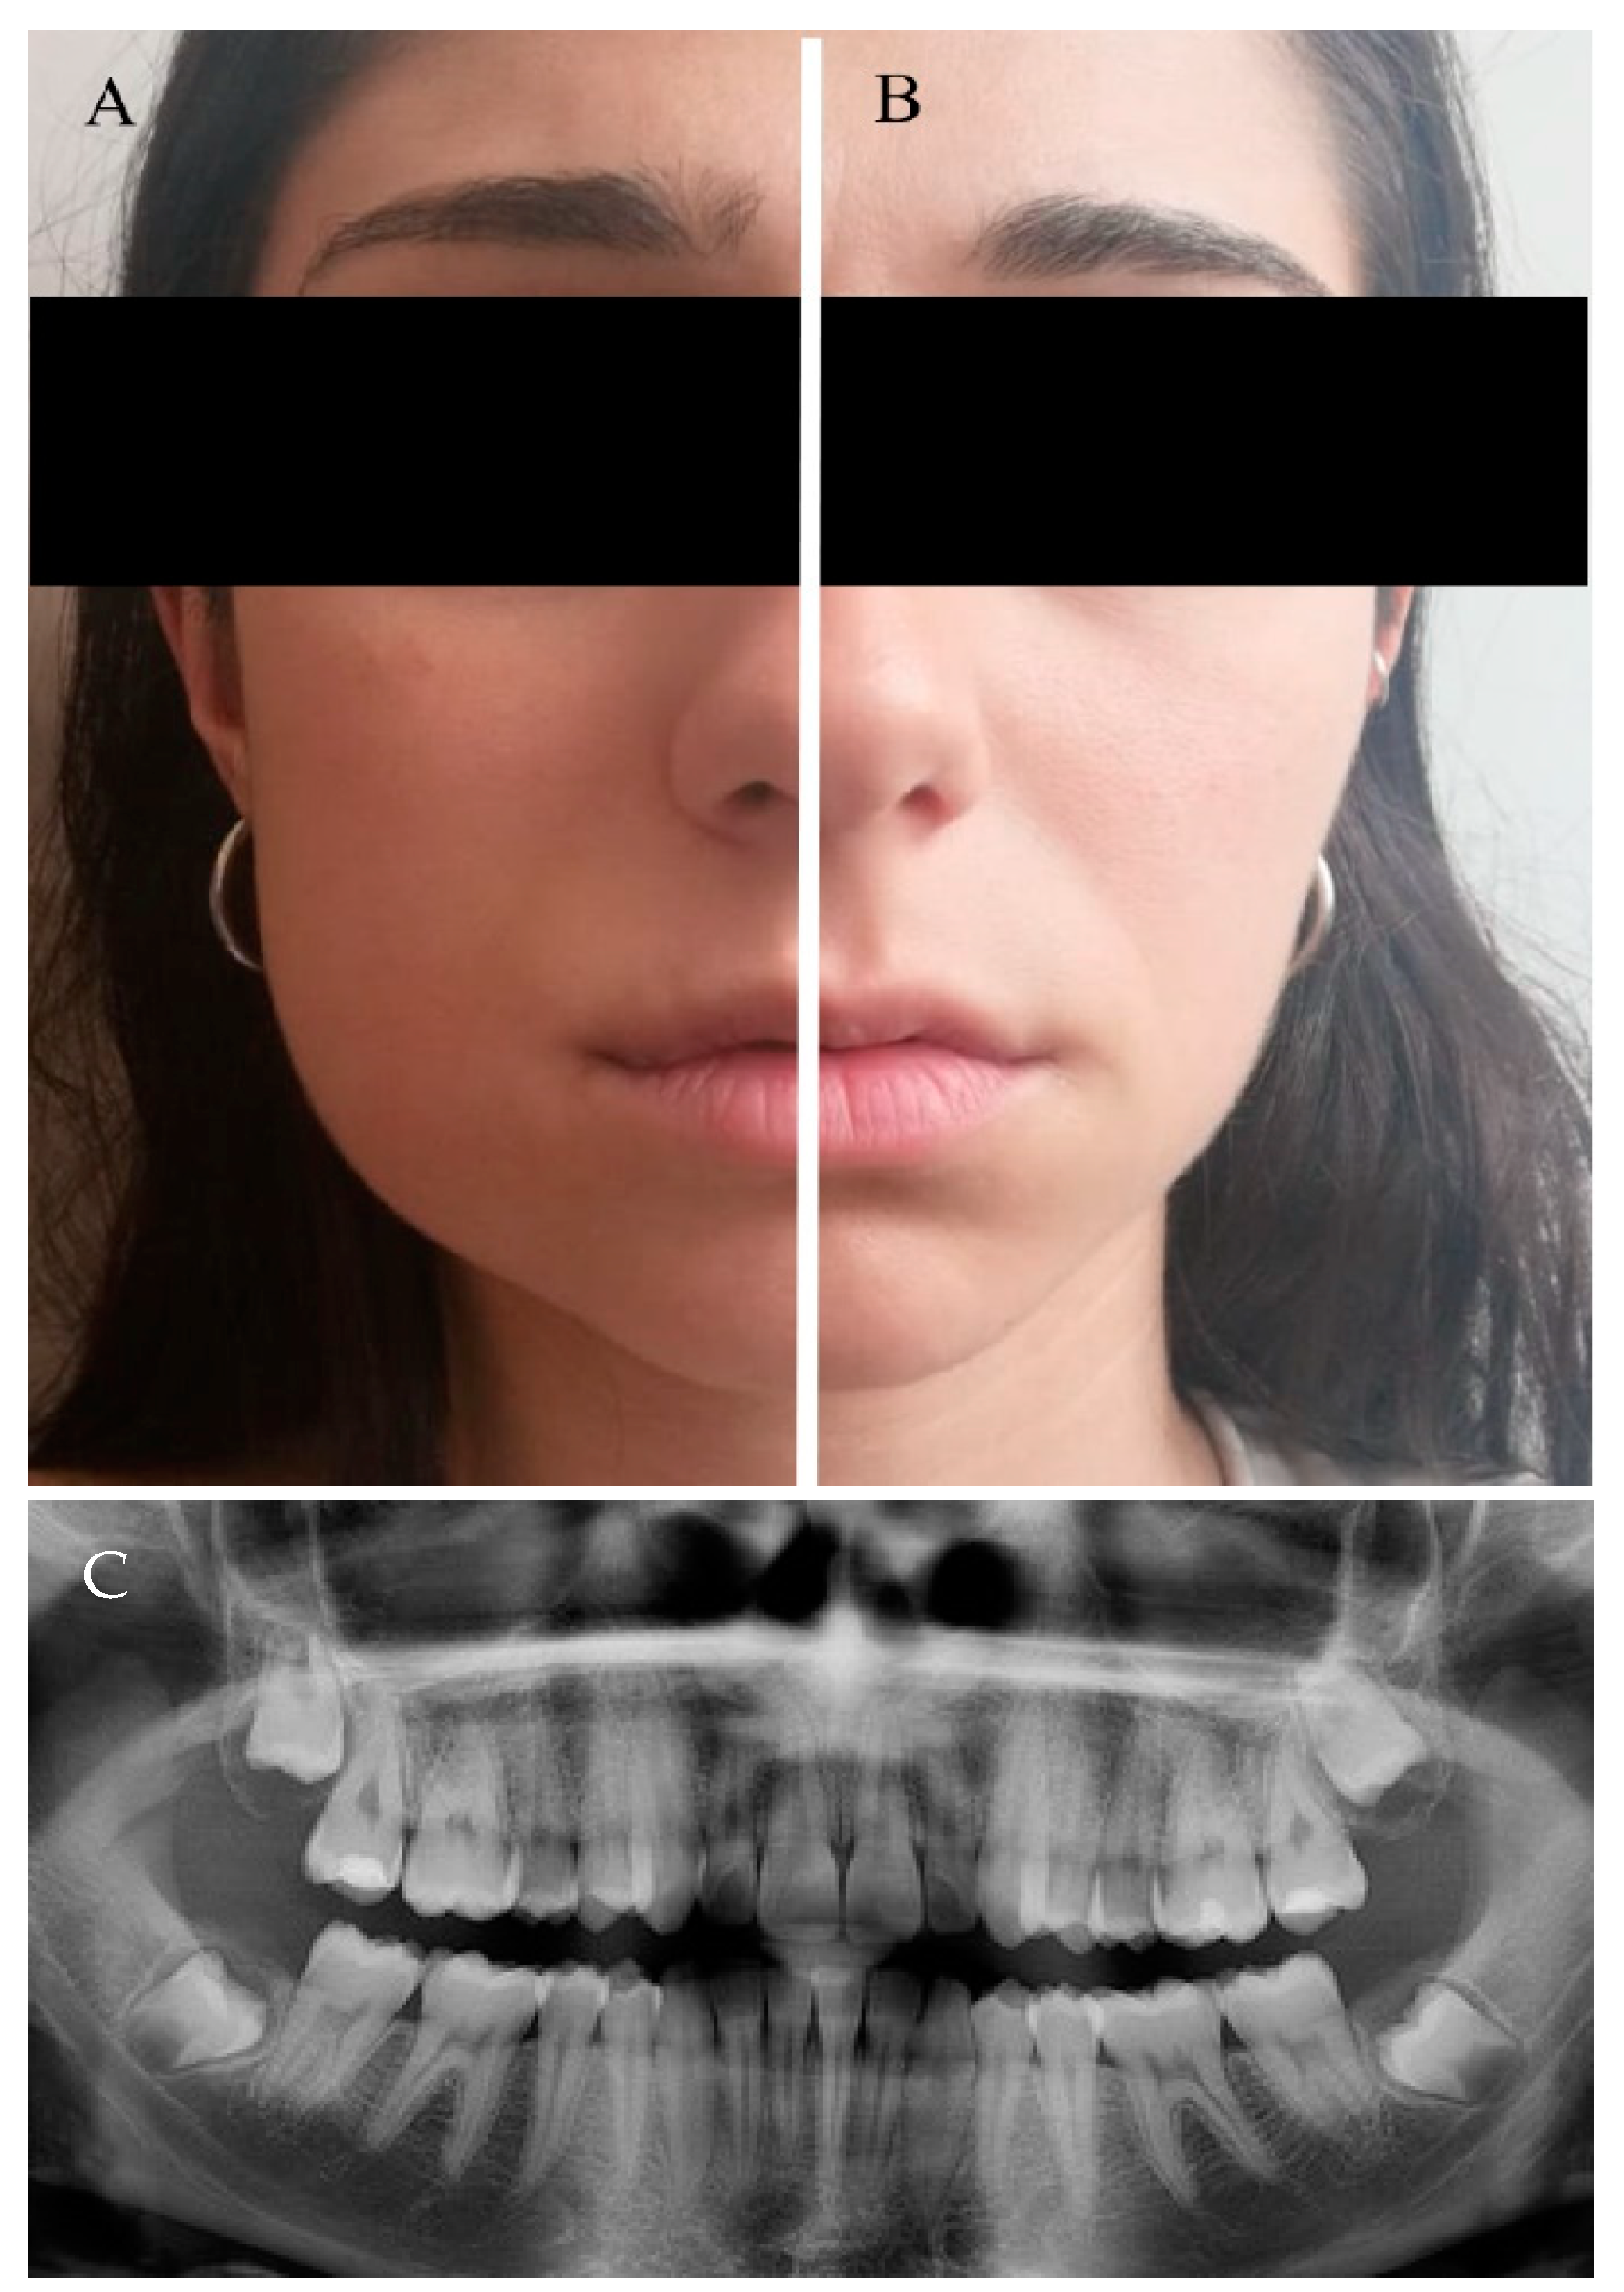

Figure 3.

Every patient was randomly treated, on the same day, by both approaches: traditional envelope flap (TA) and our flapless surgical approach (FSA). The image shows a patient with a evident oedema on the TA side (A), while oedema is not present on the FSA side (B). (C) panoramic X-ray of the patient’s teeth.

No oedema symptoms were detected 24 h after the surgical removal of Ms3 for either procedure. Conversely, the difference was observed 48 h after surgery between the TA and FSA, and the differences increased at 72 h (Table 2 and Figure 3). Similarly, by comparing the two techniques, no differences concerning the pain were observed 24 h after surgery (p > 0.05). However, at 48 h and 72 h, patients experienced a significantly higher level of pain from surgery by the TA technique than for treatment by the FSA technique (Table 2). Concerning AG, oedema and pain, the linear mixed model resulted in a statistically significant difference between the TA and FSA (p = 0.003; p < 0.01; and p = 0.018, respectively). Conversely, the model did not show a difference (p = 0.322) between the two methods if PPD was taken into account. For the GLM method, degrees of liberty and F were 8 and 5.4, 5 and 16.4, and 5 and 3.0, respectively. The FSA procedure was statistically faster than the TA procedure (17 min and 8 s (±6 s) vs. 28 min and 6 s (±4 s), respectively) (p < 0.05).